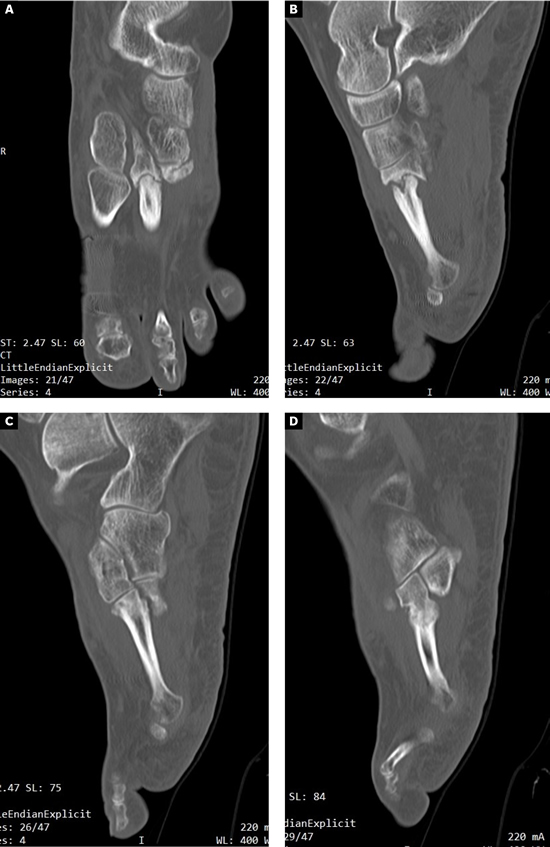

Se realizó radiografía dorso-plantar en carga del pie derecho (Figura 1) que mostraba una imagen radiológica compatible con ausencia de consolidación de las osteotomías en las bases de 2.º, 3.º y 4.º metatarsianos, además de la presencia de hallux abductus valgus. Se solicitó una tomografía axial computarizada (TAC) para estudiar más detenidamente el estado actual del proceso de consolidación ósea. La paciente acudió con resultado de TAC el 5 de mayo de 2015, donde se evidenció la ausencia completa de consolidación ósea en segundo metatarsiano (Figuras 2A y 2B), consolidación prácticamente completa de tercer metatarsiano (Figura 2C) y la presencia de callo óseo con consolidación incompleta en el cuatro metatarsiano (Figura 2D).

Figura 2. Radiografía dorso-plantar en carga del pie derecho. Se evidencia la ausencia de consolidación de las osteotomías en las bases de 2.º, 3.º y 4.º metatarsianos después de 9 meses de la intervención inicial.

Imagen 6. TAC postoperatorio a los 5 meses. 6A. Imagen del 2º metatarsiano que muestra integración del injerto con la placa dorsal. 6B. Imagen del 4º metatarsiano que muestra consolidación del 4º metatarsiano.